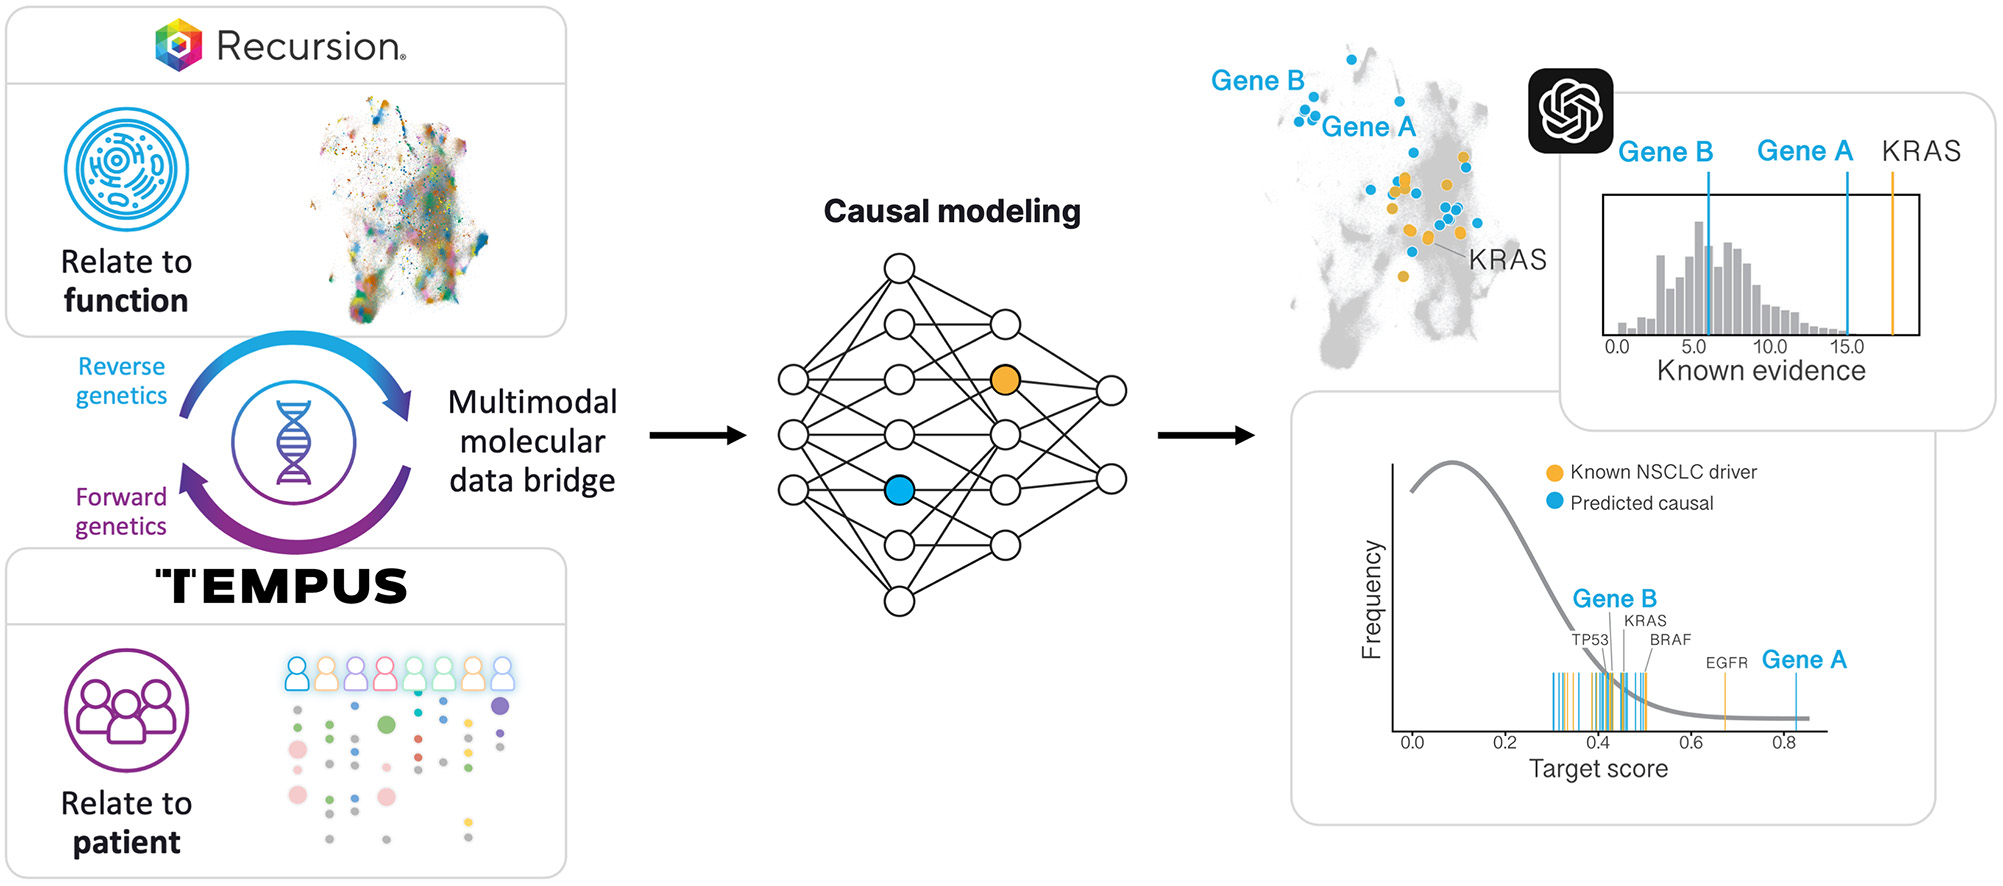

| Our Collaborators | | Partnership •Made significant progress against both the gastrointestinal-oncology and neuroscience portions of our collaboration with Roche and Genentech, including Roche exercising its Small Molecule Validated Hit Option to further advance our first partnership program in GI-oncology •Updated our collaboration with Bayer to focus on challenging oncology indications with high unmet need, commensurate with higher per program milestone payments •Entered into a collaboration with NVIDIA to accelerate the construction, optimization and deployment of foundation models for biology and chemistry as well as host Recursion-built computational and data tools on BioNeMo (NVIDIA’s drug discovery platform) – additionally, NVIDIA invested $50 million in Recursion via a private placement •Entered into a collaboration with Tempus giving Recursion access to over 20 petabytes of proprietary de-identified, multimodal patient oncology data for the purpose of training causal AI models for the discovery of novel therapeutic hypotheses, biomarker strategies and patient cohort selection •Entered into a partnership with Enamine to generate enriched screening libraries with insights from Recursion’s protein-ligand interaction predictions spanning across Enamine’s massive library of approximately 36 billion compounds Recursion OS •Built, scaled and industrialized multiple tools and technologies to heavily automate workflows across the drug discovery process, creating one of the most complete full-stack TechBio solutions •Created LOWE (Large Language Model-Orchestrated Workflow Engine) connecting wet-lab and dry-lab components of the Recursion OS using a natural language interface to streamline complex drug discovery tasks •Deployed large language models (LLMs) to map scientific literature in conjunction with our internally derived proprietary maps for the purpose of autonomously identifying novel opportunities in areas of unmet need •Deployed Phenom-1, a vision transformer utilizing hundreds of millions of parameters trained on billions of biological images from our proprietary data, which we believe to be the world’s largest phenomics foundation model at this time •Deployed new digital chemistry tools to predict the ligand-protein interactions for approximately 36 billion compounds in the Enamine REAL Space, reported to be the largest synthesizable chemical library •Produced over 1 trillion human induced pluripotent stem cell (hiPSC)-derived neuronal cells since 2022, likely making Recursion one of the world’s largest producers of neuronal cells •Began training causal AI models leveraging over 20 petabytes of multi-modal precision oncology patient data from Tempus to support the discovery of potential biomarker-enriched therapeutics at scale |

•Entered into a collaboration with Tempus giving Recursion access to over 20 petabytes of proprietary deidentified, multimodal patient oncology data for the purpose of training causal AI models for the discovery of novel therapeutic hypotheses, biomarker strategies and patient cohort selection

•Began training causal AI models leveraging over 20 petabytes of multimodal precision oncology patient data from Tempus to support the discovery of potential biomarker-enriched therapeutics at scale